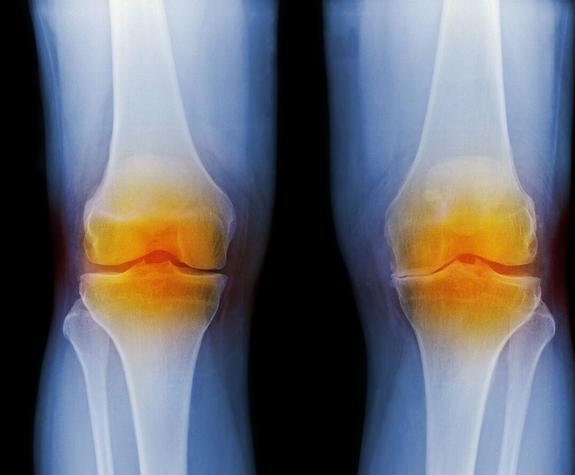

膝盖隐隐约约的疼,关节炎是怎么样个疼法?